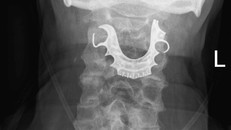

(Ngày Nay) - Một tạp chí y khoa đưa tin về trường hợp của một cụ ông 72 tuổi người Anh có răng giả bị mắc kẹt trong cổ họng hơn 1 tuần sau khi trải qua một ca phẫu thuật.